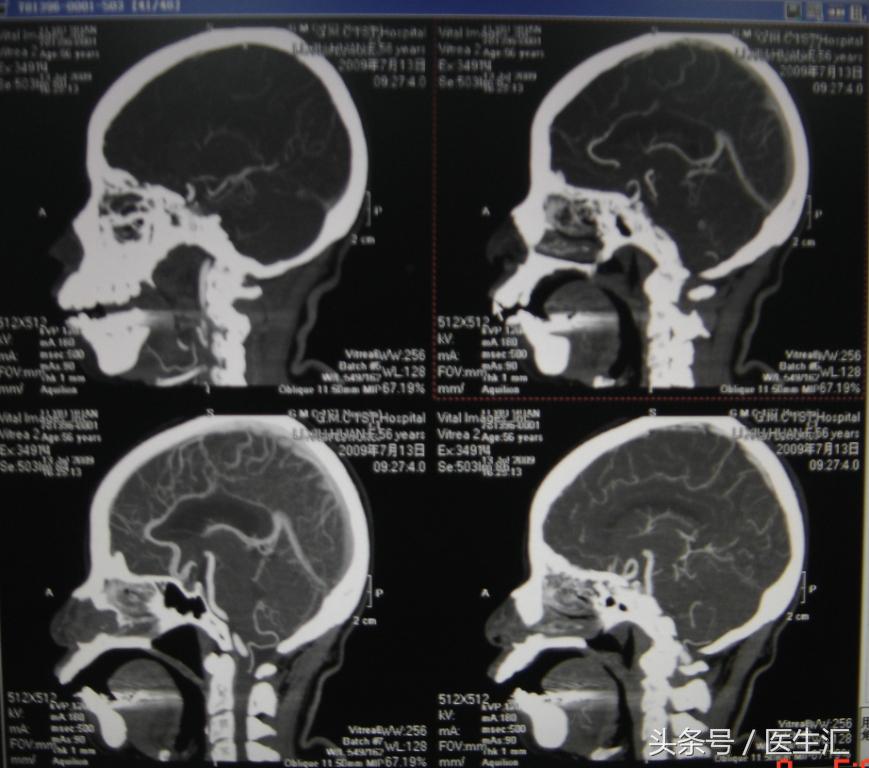

辅助检查:1、16:26CT检查平扫和灌注成像均未见明显异常(见图10、11)

2、头颅MRI、MRA及脑血管三维重建(图12、13、14)